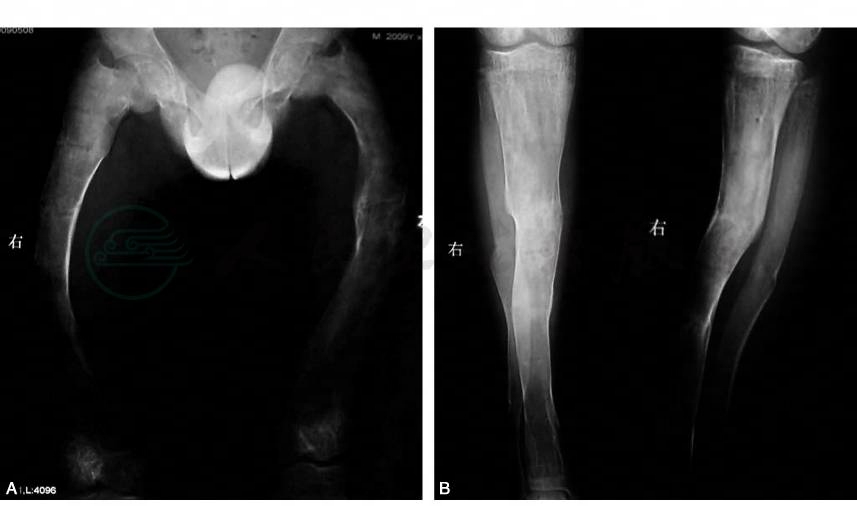

X线提示:双侧股骨和胫腓骨严重畸形,骨质呈现磨砂玻璃样改变(图2、图3)。双侧肱骨、左侧尺骨近端骨质也呈现磨砂玻璃样改变,左侧肱骨下段骨折畸形愈合。

图2 术前下肢全长片

图3 术前股骨、胫骨侧位(或斜位)片